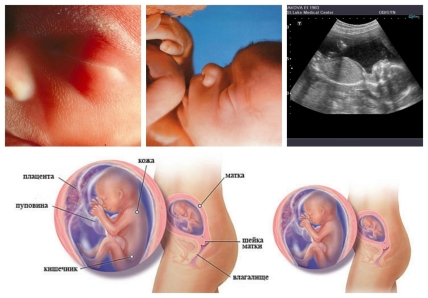

19 неделя беременности: будущий малыш весит около 170-200 г., а его рост около 15 см. Тело ребенка становится все более пропорциональным, продолжается увеличение подкожно-жировой ткани, в первую очередь она образуется за легкими, в основании шеи и вокруг почек.

Начиная с 19 недели на ультразвуковом исследовании плода можно диагностировать гидроцефалию – патологию развития головного мозга. При этом заболевании жидкость, омывающая мозг, накапливается и давит на него, мешая расти.

На 19-той неделе рост Вашего ребенка 15 см, вес 260 г, как маленький кабачок.

Кроме биохимического анализа крови второй скрининг включает в себя УЗИ, на котором врач определит размеры носовой кости плода и толщину воротничковой зоны, оценит сердцебиение плода и его двигательную активность, диагностирует отсутствие патологий, осмотрит маточный миометрий, размеры матки и плода, а также состояние околоплодных вод. Также именно на этом ультразвуковом исследовании можно узнать пол ребенка.